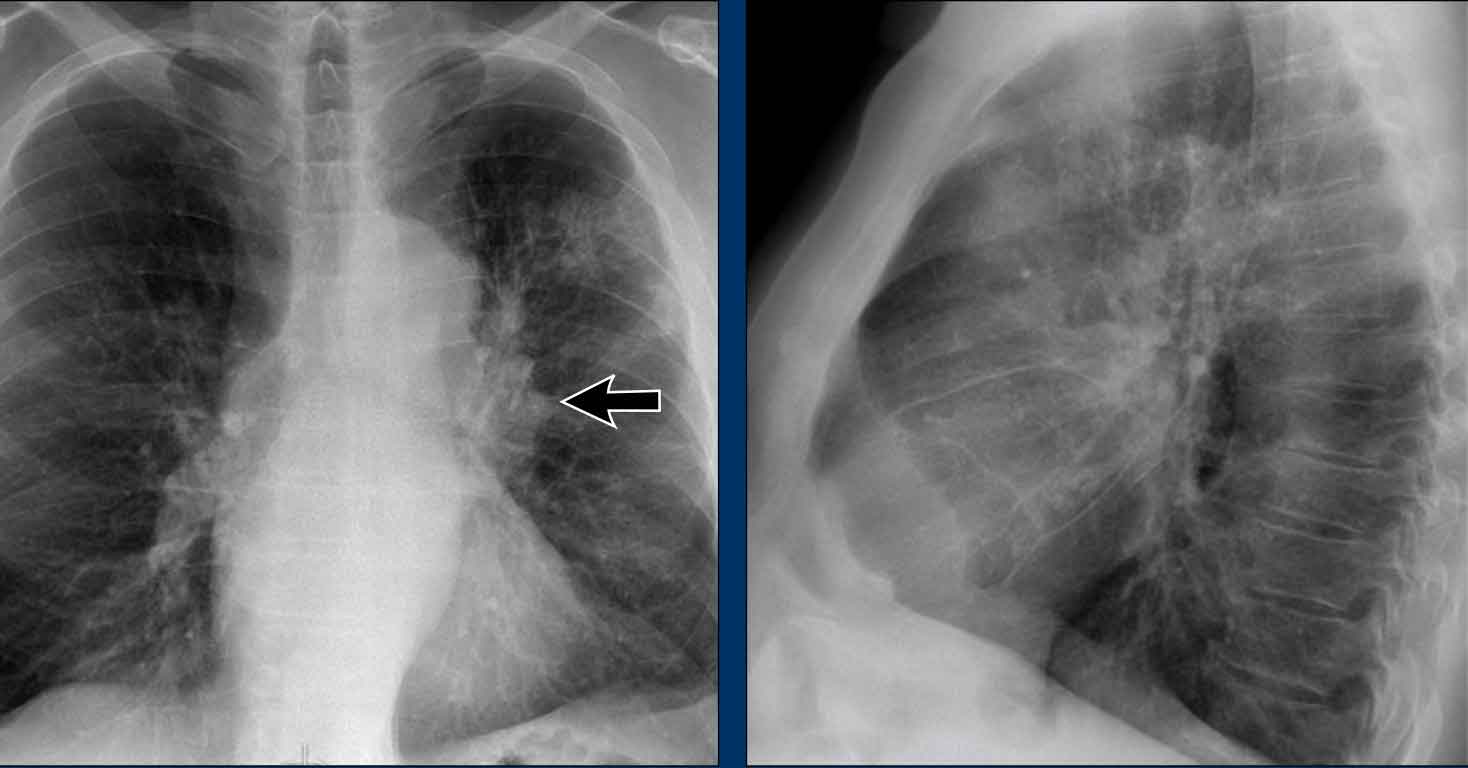

Case Example: Subtle Signs of Congestive Heart Failure

Begin by reviewing these current chest radiographs.

Based solely on these images, one might suspect congestive heart failure (CHF), though the findings are subtle.

Now review the previous study…

Scrolling between the current and prior films significantly increases diagnostic confidence in your diagnosis of congestive heart failure.

Key comparative findings include:

• Cardiac size: Slightly increased compared to the previous study; however, cardiomegaly was already present.

• Pulmonary vasculature: Mild vascular engorgement suggesting elevated pulmonary venous pressure.

• Interstitial markings: Subtle signs of interstitial edema .

• Pleural effusions: Bilateral small effusions, with subtle changes in the inferoposterior borders of the lower lobes, suggesting fluid accumulation.